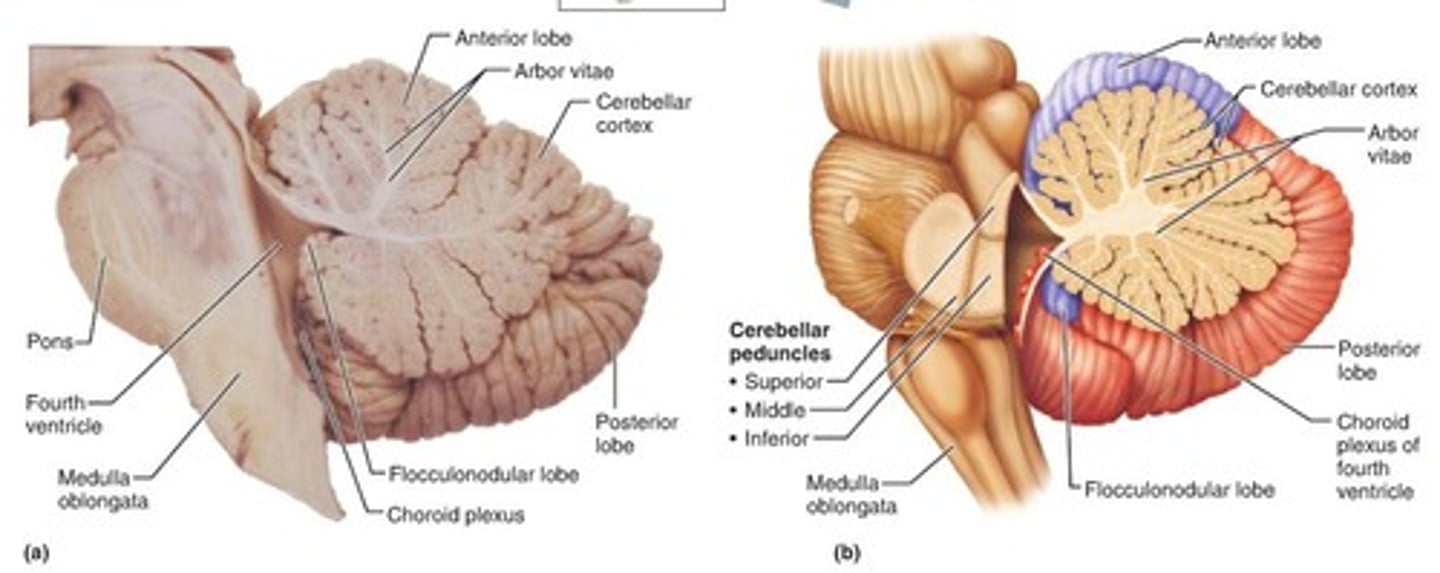

What anatomical aspect of the 4th ventricle is considered its roof?

dorsal

What forms the superior portion of the roof of the 4th ventricle? (A)

superior cerebellar peduncles

inverted V shaped interval between the superior cerebellar peduncles that is filled by a thin layer of white matter

superior medullary velum

lower portion of the roof of the 4th ventricle formed by a thin layer of pia mater and ependymal cells

inferior medullary velum

structure attached to the ventral surface of the inferior medullary velum in the 4th ventricle that helps form CSF

choroid plexus

opening in the caudal aspect of the inferior medullary velum that allows CSF from the 4th ventricle to flow into the cisterna magna of the subarachnoid space

foramen of Magendie (or median aperture)

What mostly forms the lateral walls of the 4th ventricle?

inferior cerebellar peduncles and choroid plexus

openings in the 4th ventricle that allows CSF to flow from the 4th ventricle into the pontine cistern of the subarachnoid space

foramen of von Luschka (or lateral apertures)

A

superior cerebellar peduncles

superior medullary velum

inferior medullary velum